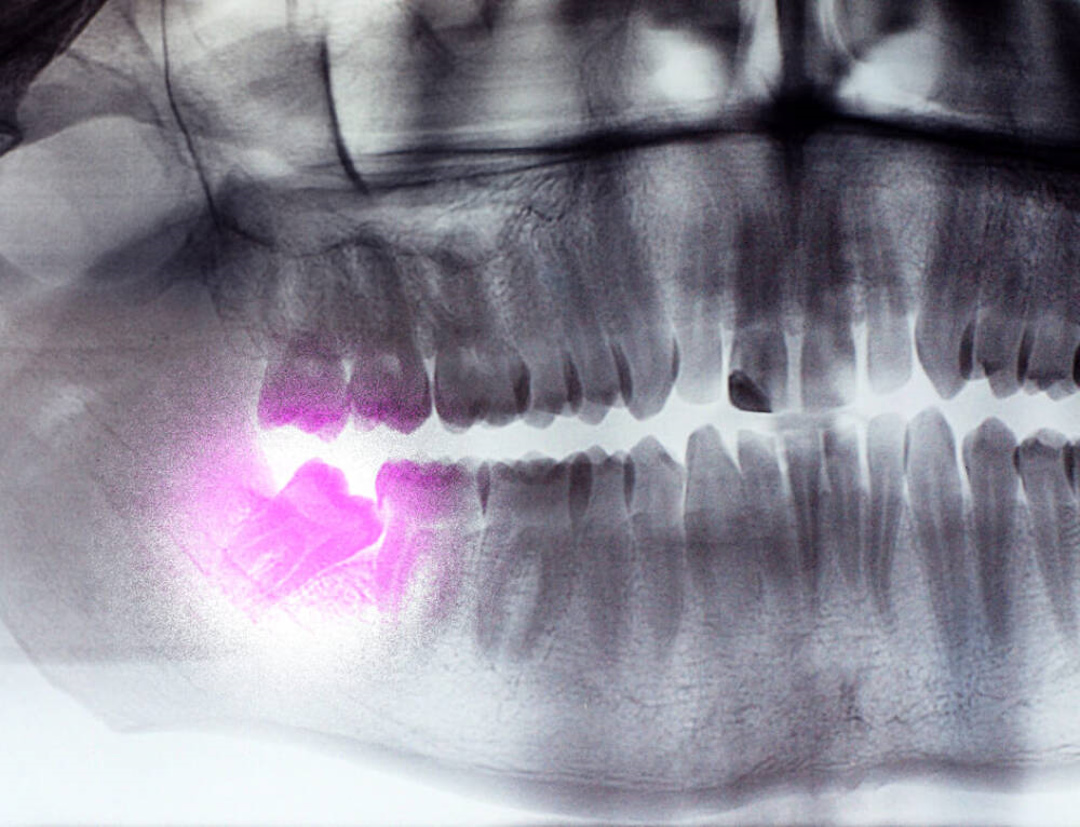

Киста – это полость с жидкостью, образующаяся у корня зуба. Она развивается бессимптомно, но при увеличении вызывает давящую боль и деформацию челюсти. Обнаруживается обычно на рентгеновском снимке.

Рентгенография – основной метод диагностики проблем с зубом мудрости. Прицельный снимок показывает состояние одного зуба, положение его корней и наличие воспаления. Процедура занимает 2-3 минуты и абсолютно безболезненна.

Ортопантомография (панорамный снимок) дает полную картину обеих челюстей. На нем видны все зубы мудрости, их положение относительно соседних зубов и нервов. Этот метод особенно важен перед планированием удаления.

В сложных случаях назначают компьютерную томографию. Трехмерное изображение позволяет увидеть точное положение корней, их близость к нервам и гайморовой пазухе. КТ необходима при планировании сложного удаления дистопированного зуба.

Диагностика помогает врачу принять обоснованное решение – лечить или удалять. Она также предотвращает осложнения во время операции и позволяет спланировать оптимальный метод вмешательства.